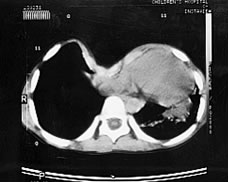

Pectus excavatum is a pectus deformity. In pectus excavatum (funnel chest) the sternum (breastbone) is depressed in a concave shape. There may be asymmetry of the chest and the sternum may be rotated. The deformity varies in severity, ranging from a mild indentation/protrusion to severe, for example, a patient with a severe pectus excavatum may have only a few centimeters between his/her sternum and vertebral column. Severe cases of pectus excavatum can eventually interfere with the function of the heart and lungs. Most patients have a slim chest, a slouching posture and younger children commonly have potbellies. Pectus deformities are very common and can be found in approximately one out of every 400 people across the world. These deformatries are more frequently found in boys than girls, 4:1.